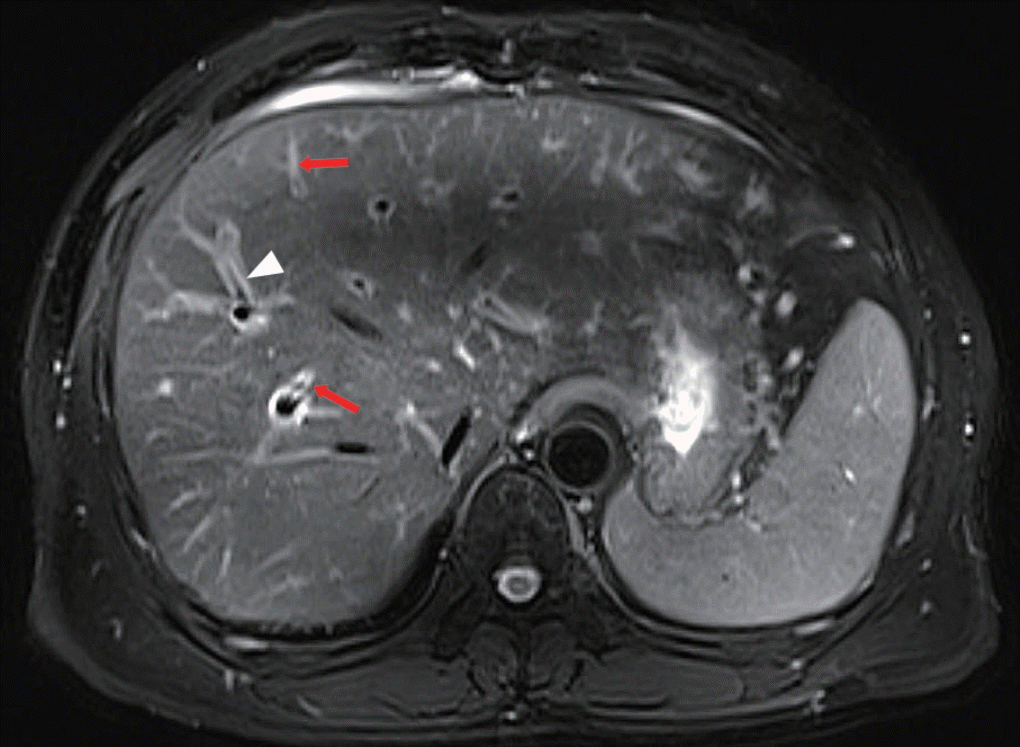

The laboratory data showed white blood cells 11.61×109/L (WBCs, normal=3.5-9.5×109/L), with an eosinophil count of 5.78×109/L (normal=0.02-0.52×109/L) and an eosinophil percentage of 50% (normal=0.4-8%). AST 67 U/L (normal=15-40 U/L), ALT 211.9 U/L (normal=9-50 U/L), γ-GT 677 U/L (normal=10-60 U/L), total bilirubin 229.7 μmol/L (normal=6.8-30 μmol/L), and direct bilirubin 143.1 μmol/L (normal=0.0-8.6 μmol/L) were also detected. Viral marker assessment revealed HBs Ag (-), anti-HBs Ab (+), anti-HAV IgM (-), and anti-HCV Ab (-), and serum tumor markers were normal. Stool examinations for eggs by direct smear were negative 3 times. MR cholangiopancreatography (MRCP) showed cholecystitis, mild dilatation of the intrahepatic duct, and increased periductal echogenicity along the diffuse dilated bile ducts (Fig. 1), but no space-occupying lesions. A CT scan revealed the same changes as on the MRCP.

In addition, non-invasive radiologic examinations, such as MRCP and CT, make remarkable contributions to diagnosis of clonorchiasis. Dilation, increased periductal echogenicity, and stricture of the intrahepatic bile ducts can be attributed to changes due to C. sinensis infection [5,12], but non-specific. Some of imaging findings in the present report were in line with reported presentations, without other causes of obstructive jaundice, such as stones or space-occupying lesions. The only possible explanation of jaundice was that the infiltration by inflammatory cells and the bile duct wall thickening might have caused the bile duct stricture, leading to painless jaundice. In this case, the stool examination by direct smear and images did not reveal the obvious diagnostic indications, while the patient’s jaundice was not relieved after liver-protective treatment. Based on these reasons, liver biopsy was performed to speed up diagnosis and avoid the missed diagnosis of serious diseases. However, waiting for the results of the other methods of stool examination may be more appropriate.